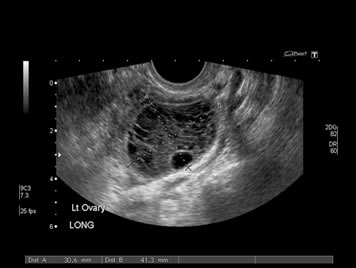

Testicular or scrotal scan is done to diagnose cause of pain or swelling in the testes such as inflammation or torsion and also to diagnose cause of infertility such as varicocele etc.